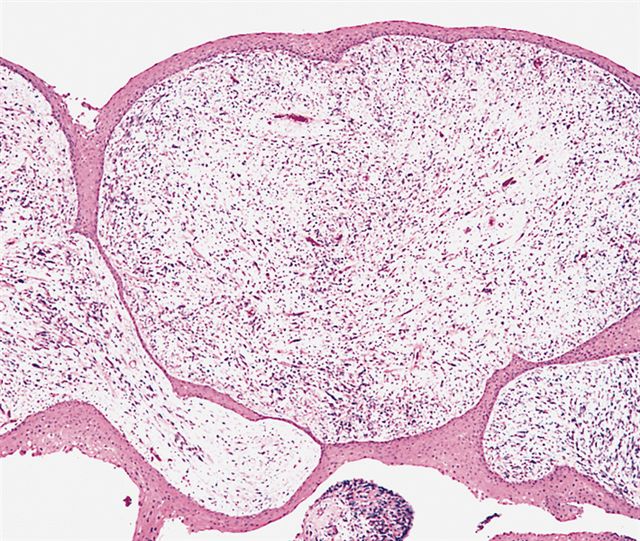

Microscopic (histologic) images

Contributed by Erdener Özer, M.D., Ph.D. and Mark R. Wick, M.D.

Contributed by Carolina Martinez Ciarpaglini, M.D., Ph.D. (Case #276) - tonsillar mass

AFIP images - botryoid variant